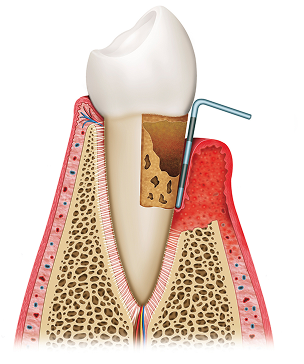

잇몸 질환 치료 방법

비수술적 잇몸 치료 - 치주 소파술

잇몸 아래 치아 뿌리 부위까지 치석이 내려간 경우, 국소마취 또는 수면마취 하에

‘큐렛(curette)’이라는 전용 기구로 치석과 염증 조직을 정밀하게 제거합니다.

수술적 잇몸 치료 - 잇몸 수술

치아 뿌리 깊숙이 자리한 치석을 비수술적 치료만으로 제거하기 어려울 때,

잇몸을 절개해 직접 시야를 확보한 뒤, 숨어 있는 치석과 염증 조직을 깨끗이 제거하는 치료입니다.

치주조직 재생 치료제, 엠도게인

엠도게인®은 잇몸 조직(잇몸, 잇몸뼈)의 재생을 돕는 치료제입니다.

단백질 겔 형태의 엠도게인은 치아가 처음 형성될 때의 자연 신호를 모방해

치아 뿌리 주변에 새 살(백악질, 치주 인대, 잇몸 뼈)이 자라나도록 유도합니다.

일반적인 잇몸 치료나 수술은 치석을 제거해 병의 진행을 멈추는 데 초점을 두지만,

엠도게인®을 적절히 사용하면 이미 손상된 잇몸 조직이 다시 채워지는 효과를 기대할 수 있습니다.